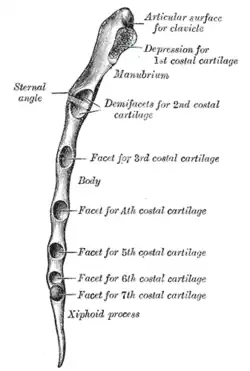

Superfície posterior do esterno. | |

Superfície anterior do esterno e cartilagens costais.

Superfície anterior do esterno e cartilagens costais. -